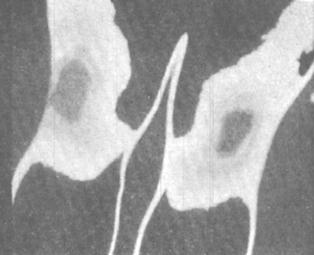

Рис. 8.42. Термограмма коленных суставов (артроз)

Рис. 8.43. Термограмма коленных суставов (артрит)

Тепловое действие невидимых инфракрасных лучей, излучаемых тканями суставов, регистрируется с помощью тепловизоров (термографов). Эти аппараты создают четкую картограмму поверхностной температуры тела, где «теплые» и «холодные» участки имеют различный цвет. Для определения точной количественной характеристики термограмм пользуются специальными стандартными эталонами. Учитываются такие показатели, как площадь симметричных и асимметричных участков, областей гипо- и гипертермии, степень однородности изотермических зон. Термограммы у здоровых людей характеризуются равномерным снижением уровня теплового излучения овальной формы с четкими контурами или наличием одного-двух светлых участков по внутренней стороне сочленения. Различия температуры в симметричных участках не превышают 0,5°С.